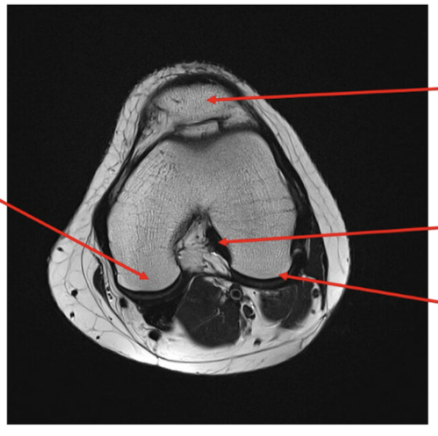

label each

2- lateral and medial condyles of femur

4- vastus lateralis muscle

5-posterior cruciate ligament

6- anterior cruciate ligament

7- medial meniscus of knee

8- lateral meniscus of knee

9-tibia

10-fibula